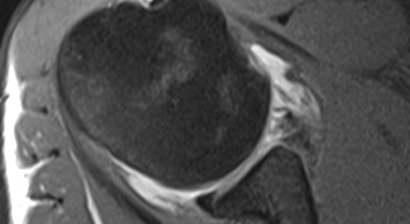

Impingementsyndrom der Schulter

Das Impingement-Syndrom stellt ein Einklemmen unterschiedlicher anatomischer Strukturen im Bereich der Schulter dar. Dies kann verschiedenste Ursachen haben. Das sogenannte „subacromiale Impingement“ ist die vermutlich häufigste Form des Impingementsyndroms. Hierbei kommt es zu einem Engpasssyndrom...